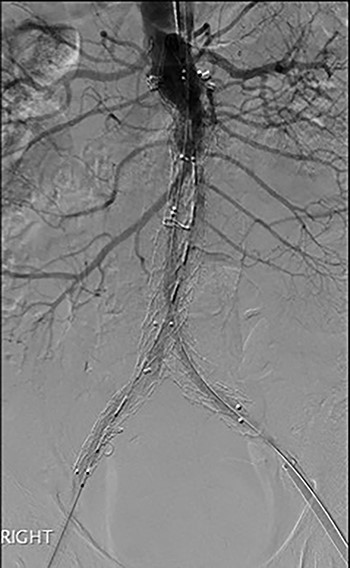

Post-lysis CT scanning showing fully re-canalized aorto-iliac system.

The patient was transferred to the high-dependency unit for observation during the thrombolysis. After 4-h, the patient was taken back to Interventional Radiology department for a check angiogram (Fig. 3). This demonstrated a fully re-canalized aorto-iliac system with no distal thrombotic or embolic complications. The thrombolysis infusion was stopped at this stage. In the post-operative period, anticoagulation has been continued with Apixaban. A CT scan 6 weeks post-procedure has confirmed ongoing patency of the endograft with no visible thrombus (Fig. 4).